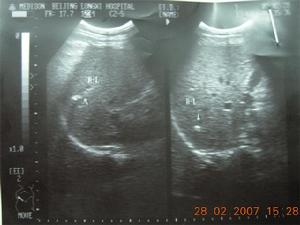

陶瓷樣膽囊2.腹部B超B超及CT檢查是發現無症狀陶瓷樣膽囊的主要方法。B超可見膽囊壁呈強回聲、後方伴聲影,膽囊壁可增厚。B超下陶瓷樣膽囊分為3型:Ⅰ型,也稱硬化萎縮期,為回聲增強的半月狀結構伴後方聲影,類似於一個充滿石頭而無膽汁的收縮膽囊。Ⅱ型,為雙凸狀曲線結構伴可變聲影,但聲波衰減較Ⅰ型輕,因而可觀察到膽囊的前後壁,該型常常能見到膽囊內結石。Ⅲ型,為不規律塊狀回聲伴後方聲影。Ⅰ型為病理分型中的完全鈣化型,發生癌症的幾率低或沒有。Ⅱ型和Ⅲ型為不完全鈣化型,易並髮結石和膽囊癌。